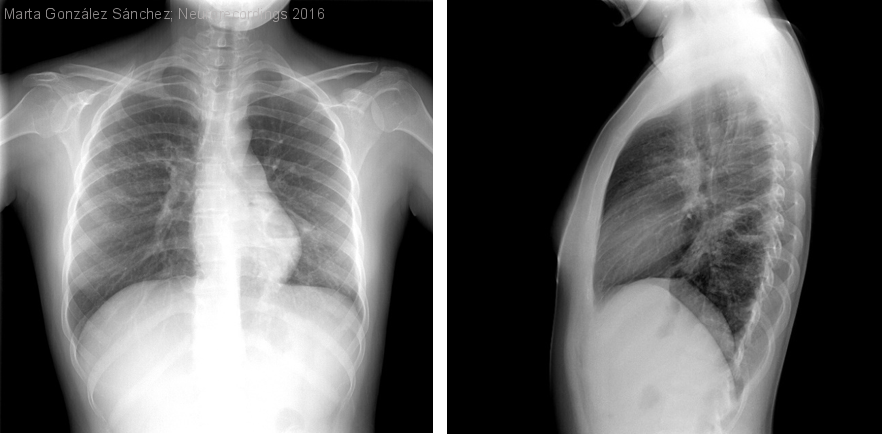

Absceso por Mycobacterium tuberculosis

Mujer | 18 años

Resumen del caso

Mujer de 18 años natural de Perú, sana. Ingresa en el hospital por presentar una crisis comicial parcial compleja secundariamente generaliza aislada y cefalea holocraneal, sin otra clínica acompañante. La exploración cardiopulmonar y neurológica fue...